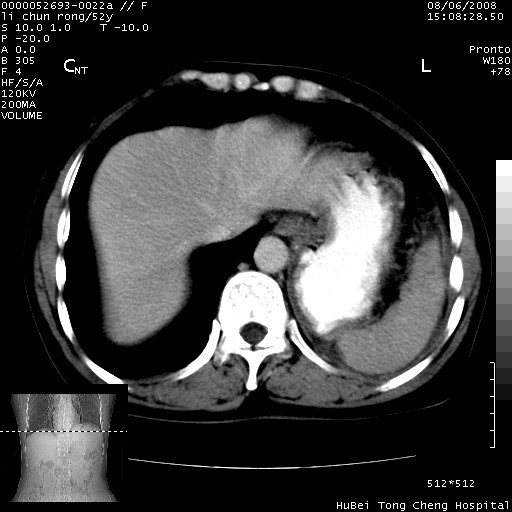

以下是引用云翔在2008-8-7 6:20:00的发言:[br]胰尾部囊性病变,考虑假囊肿,结合实验室检查疾病史

以下是引用zjzjr在2008-8-7 8:38:00的发言:[br]支持胰腺炎伴假囊肿形成,左肾小囊肿.少量腹水.

以下是引用随光逐影在2008-8-7 9:12:00的发言:[br]1)考虑胰腺炎伴假性囊肿形成可能性大;胰腺囊腺瘤待排。2)左肾小囊肿。3)少量腹水。